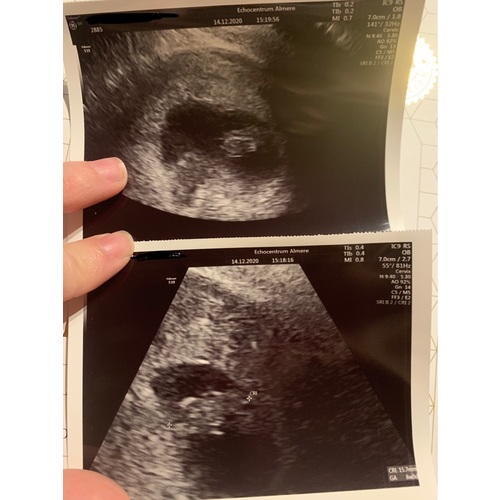

Ik dacht 8 weken te zijn bij de echo ze hadden me alleen iets terug gezet naar 7+4. Nu alweer een goede termijn echo gehad en vandaag alweer 11+4.

Helaas moeilijk tezien gisteren echo gehad ban 8+5 maar mijn baarmoeder ligt nog wat verder naar achter dus niet zn hele helderen echo maar hartje klopt en alles was goed 😍😍